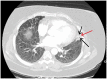

We present the case of a 56-year-old woman who was diagnosed with severe coronavirus disease 2019 (COVID-19) pneumonia complicated by severe acute respiratory distress syndrome who was intubated for 19 days. She recovered from COVID-19 after a month. A computed tomography (CT) scan of the chest, after a month, showed improved infiltrates with a small residual cavity within the lingula. A CT angiogram showed a more confluent density in the lingular portion on follow-up 2 months later. She developed intermittent hemoptysis after 3 months in December 2020, which persisted for almost 6 months, and CT of the chest showed the lingular nodular with resolution of the cavitation. She underwent bronchoscopy with bronchoalveolar lavage, confirming Aspergillus fumigatus by galactomannan assay and histology showing branching hyphae. Once she started treatment with itraconazole, her hemoptysis resolved. The follow-up CT of the chest after 2 months of treatment did not show a cavity or a nodule in the lingula. Our patient developed invasive pulmonary aspergillosis (IPA) as a sequela of severe COVID-19 infection. COVID-19-associated invasive pulmonary aspergillosis (CAPA) is an underrecognized complication that needs to be investigated on whether prophylactic treatment is required. Our case also demonstrates that the diagnosis of IPA needs to be considered months after COVID-19 infection when a superimposed fungal infection can occur after a viral infection if the patient continues to have persistent symptoms.